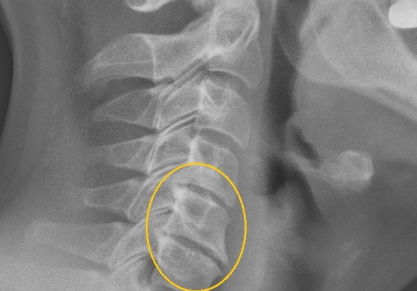

Данное поражение суставов является самым распространенным среди взрослого населения. Оно развивается у любого человека, независимо от возраста (может появляться не только у пожилых людей, но также и у молодежи), пола. Это целый комплекс дистрофических поражений хрящевой ткани. Болезнь имеет характерную особенность — она поражает чаще всего межпозвоночные диски.

Чаще всего это заболевание считается главной причиной появления болевого синдрома в спине. Впервые почувствовать развитие болезни можно уже в 20 лет. Далее, она очень быстро прогрессирует и становится только хуже. Боль является следствием того, что хрящ, который обеспечивает амортизационные свойства позвоночника, истончается. Диски сильно прижимаются друг к другу и поддаются трению, доставляя человеку дискомфорт.

3. Остеохондроз шейного отдела.